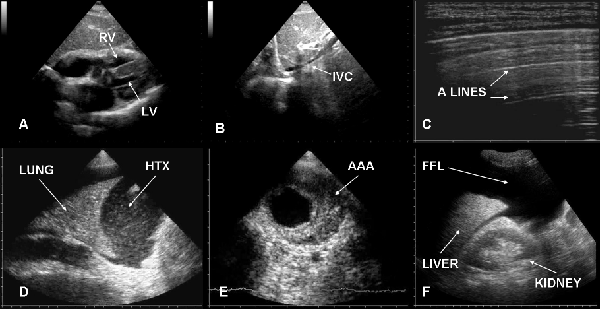

| Figure 9: Ultrasound in cardiac arrest does to hypovolemia. Typically cardiac chambers are small and hyperkinetic (A), inferior vena cava is slight (B) and lung is “dry” (C). Ultrasound can also detect some causes of hypovolemia such as large hemothorax (D), abdominal aortic aneurysm (E) or abdominal free fluid (F). RV=right ventricle, LV=left ventricle, IVC=inferior vena cava, HTX=hemothorax, AAA=abdominal aortic aneurysm, FFL=free fluid. |